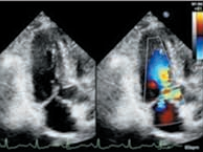

肥厚的左心室壁

二尖瓣運動曲線

左室流出道彩色血流

左室流出道血流速度